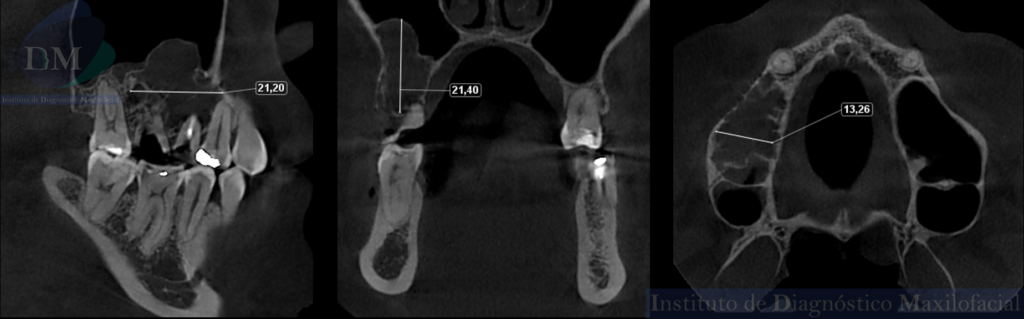

CORTES TRANSAXIALES

CORTES AXIALES

TAMAÑO

Así mismo en la tomografía volumétrica de haz cónico se evidencia un borramiento parcial de laminas duras, de las piezas 14, 15 y 17. Presentando un tamaño aproximado de 21,20 mm x 21,40 mm x 13,26 mm e invadiendo parte del seno maxilar derecho.